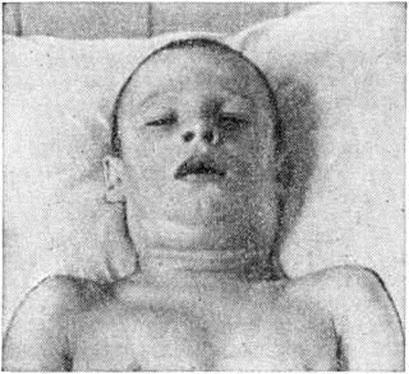

Токсическая форма (токсическая Дифтерия) в большинстве случаев начинается бурно: температура поднимается до 39° и выше, появляются головные боли, выраженная слабость, расстройство сна, анорексия, иногда рвота и боль в животе. Изредка отмечаются явления возбуждения или выраженная вялость, адинамия. Иногда при наличии тяжёлого процесса в зеве общие клин, проявления интоксикации выражены умеренно, самочувствие нарушается относительно мало. Умеренная боль при глотании. В зеве — распространённые налёты. На 2—3-й день болезни поражение зева принимает весьма характерный вид: слизистая оболочка мягкого неба, глотки отёчна, но гиперемирована относительно слабо; миндалины резко увеличены и нередко почти соприкасаются друг с другом; их поверхность выстлана толстыми бугристыми налётами белого и грязно-белого цвета, распространяющимися на мягкое и твёрдое небо (цветной рисунок 3). Язык обложен, губы сухие, потрескавшиеся. Из зева ощущается специфический неприятный сладковато-гнилостный запах. Иногда процесс распространяется на носовую часть глотки и полость носа; появляются обильные серозные, серозно-кровянистые выделения из носа. Кожа около носовых отверстий и на верхней губе экскориируется. Одновременно с развитием процесса в зеве или несколько позже в области верхне-шейных лимфатический, узлов появляется болезненный инфильтрат плотноватой консистенции с расплывчатыми контурами. Над поражёнными лимфатический, узлами и в их окружении на большем или меньшем протяжении мягкие ткани (подкожная клетчатка) отёчны (рисунок 4). Кожные покровы над отёчными тканями сохраняют нормальную окраску. Надавливание в области отёка безболезненно и не оставляет ямок; при толчкообразном ударе пальцем ткани сотрясаются наподобие желе или студня (симптом «желе», описанный С. Дифтерия Носовым в 1957 год). Распространённость отёка подкожной клетчатки соответствует выраженности интоксикации, поэтому ею руководствуются для разделения токсической дифтерии на три степени: I степень — распространение отёка до середины шеи, II степень — до ключицы, III степень — ниже ключицы. В первые дни болезни глубокая интоксикация у значительной части больных не проявляется. Отмечаются тахикардия, повышенная возбудимость сердца и обычно несколько повышенное АД Различные тяжёлые последствия интоксикации (резко выраженные расстройства со стороны нервной и сердечно-сосудистой систем) развиваются к концу первой или, чаще, на 2-й недель и позже.

Рис. 4. | ||